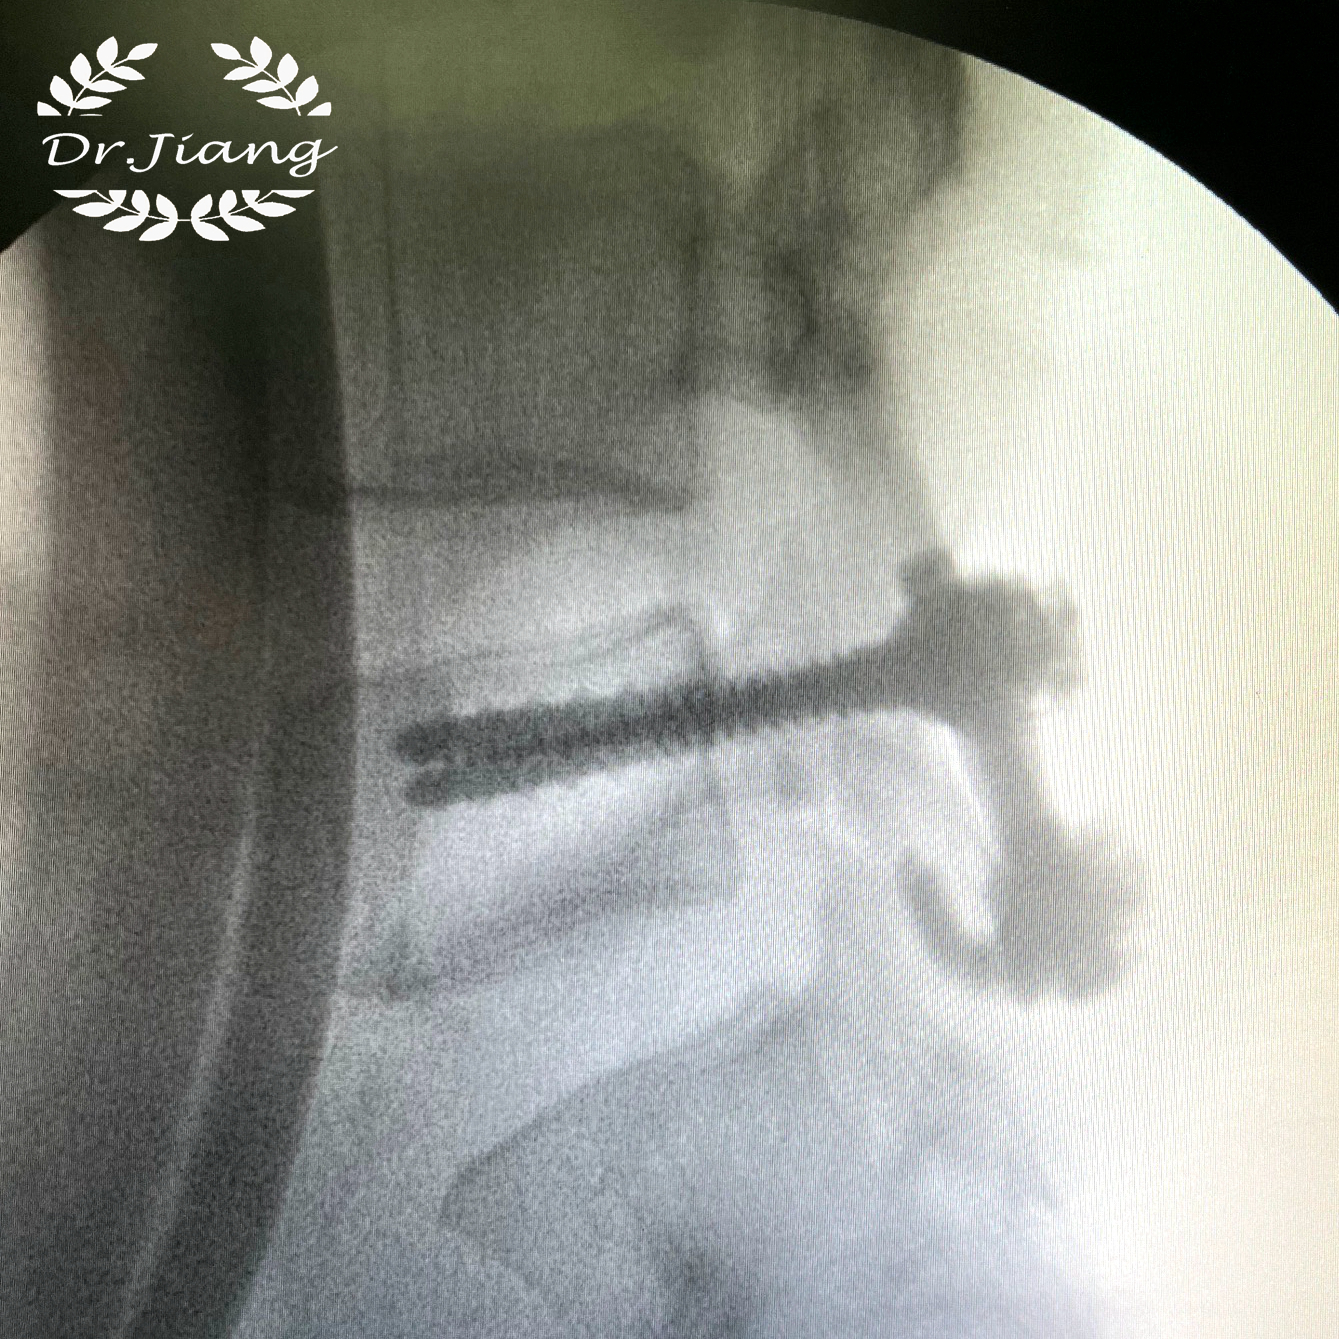

对于保守治疗超过半年但腰痛症状持续不缓解或症状较为严重的患者,通常建议根据患者病情制定个体化手术方案,及时手术干预。

钉钩技术修复峡部裂